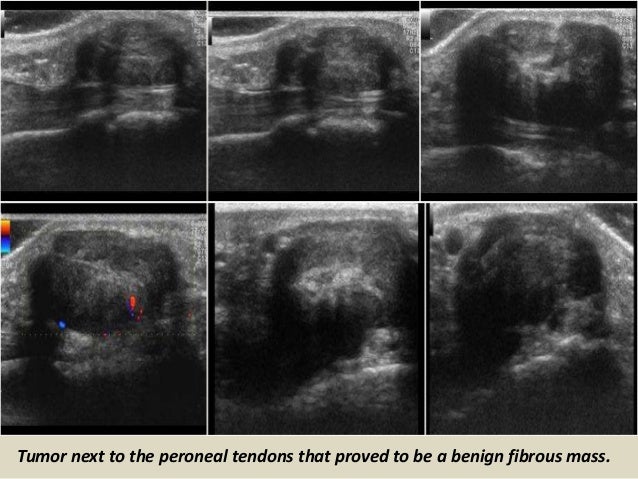

Tumor next to the peroneal tendons that proved to be a benign fibrous mass.

50. 50. Tumor next to the peroneal tendons that proved to be a benign fibrous mass.